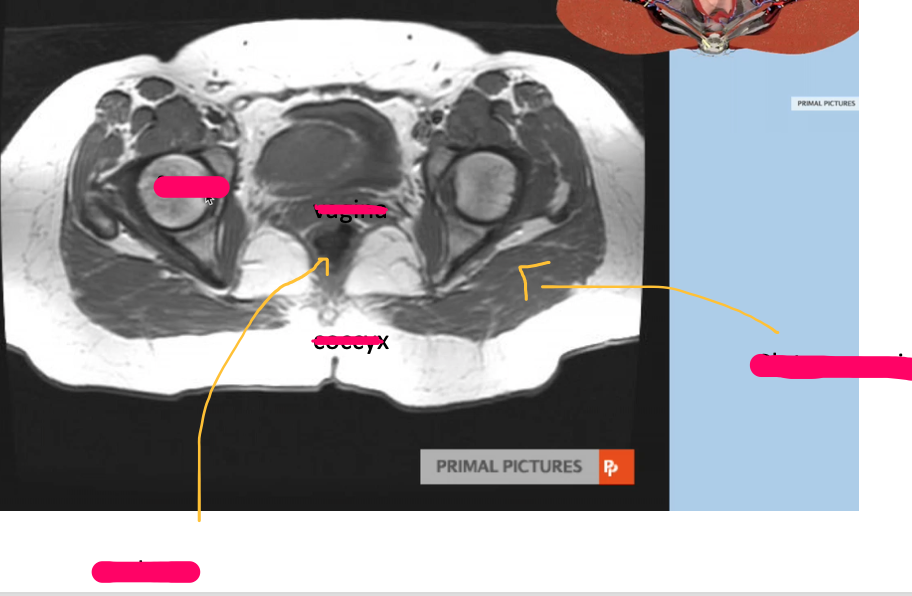

What type of imaging modality is this & fill in the blanks

MRI prostate, axial